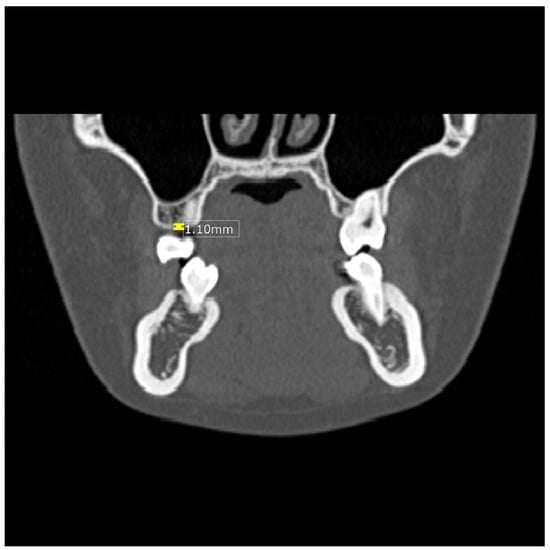

Measurements of the thickness of the alveolar crest cortical bone (Figure 1) were taken in the coronal plane from four sites: thickness between the maxillary canine and first premolar (Tmax3), thickness between the mandibular canine and first premolar (Tman3), thickness between the maxillary premolar and first molar (Tmax6), and thickness between the mandibular premolar and first molar (Tman6). Likewise, the densities of the CT values (Figure 2) between the maxillary canine and first premolar (Dmax3), the mandibular canine and first premolar (Dman3), the maxillary premolar and first molar (Dmax6), and the mandibular premolar and first molar (Dman6) were also obtained in the axial plane.

Figure 1.

Image showing measurement of the thickness (mm) of the alveolar crest cortical bone in the maxilla.